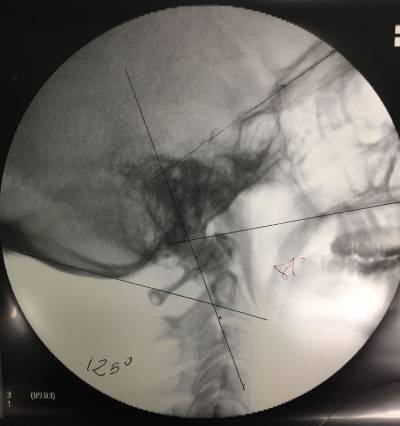

Preoperative and individualized evaluation of each case is extremely important since anomalies in the anatomy and trajectory of the Vertebral Artery should be ruled out. Anatomical differences in regard to dimensions and disposition of vertebral pedicles, lateral masses and other bone elements should also be assessed. The diagnosis can be made by means of an Upright MRI (Magnetic Resonance Imaging) or with a cervical CT scan with 3D reconstruction. Both tests should evaluate the movements of the occipitoatlantoid and atlantoaxial joints. Flexion-extension and cervical rotation on both sides should be evaluated. Lateral cervical x-ray and flexion-extension views can give us complementary information in regards to atlantoaxial instability, although it does not seem indicated as the first choice method of diagnosis. Another diagnostic method used is cervical cineradiology, which records joint(s) movement of the entire occipitocervical, atlantoaxial and subaxial joint system.

Once in the Operating Room, surgery is performed under general anesthesia, with Neurophysiological monitoring (SSEP – somatosensory evoked potentials), neuronavigation guidance and intraoperative fluoroscopy guidance.